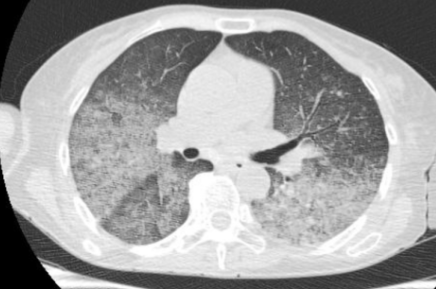

2024-6-26胸部CT影像

给予高流量氧疗(流量30L/min,氧浓度70%)、改用卡泊芬净进行抗真菌治疗。支气管镜检查显示,患者的气管、隆突、左肺及右肺各级支气管管腔内有大量白色稀薄痰液涌出。尽管进行了积极治疗,但一周后复查胸部CT发现,患者的双肺仍呈“大白肺”样改变,病变范围扩大,密度增加。提示不排除肺水肿可能……